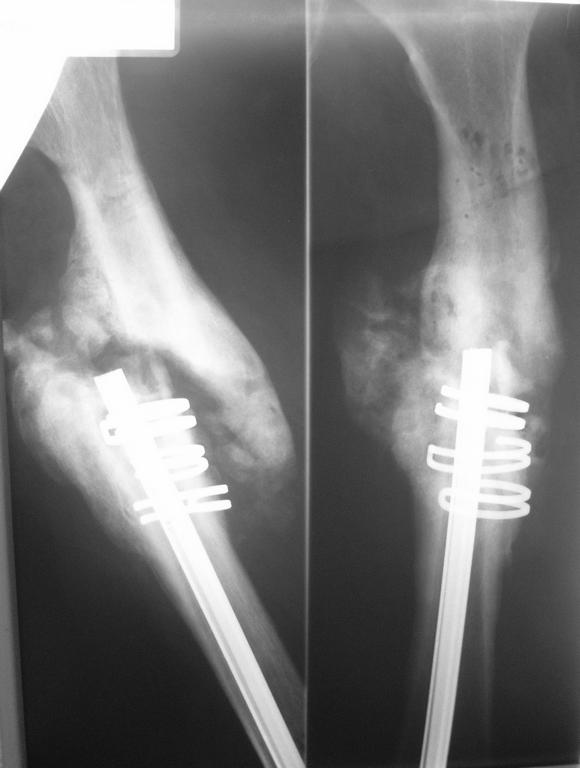

В декабре 2006г политравма в результате ДТП,соп.дз: Закрытый

винтообразный оскольчатый перелом с/з правого бедра. Выполнена

открытая репозиция, остеосинтез гвоздем Кюнчера + кольца NiTi. Через

15мес штифт сломался, был наложен АВФ, осложнением которого явился

остеомиелит бедренной кости.